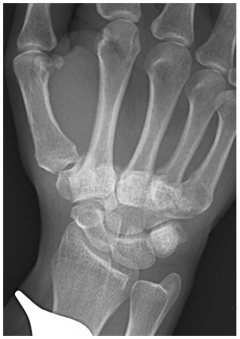

Figure 1 Dislocation of all lesser CMC.

Plain x-rays remain the gold standard for diagnosis and classification of CMCJ dislocation.5 A postero-anterior (Figure 2), oblique and lateral view series is often adequate to make the diagnosis. In unclear situations other further views or specialist imaging may be warranted. A systematic examination of the whole radiograph is mandatory to pick these injuries.14

Figure 2 PA radiographs of the hand.